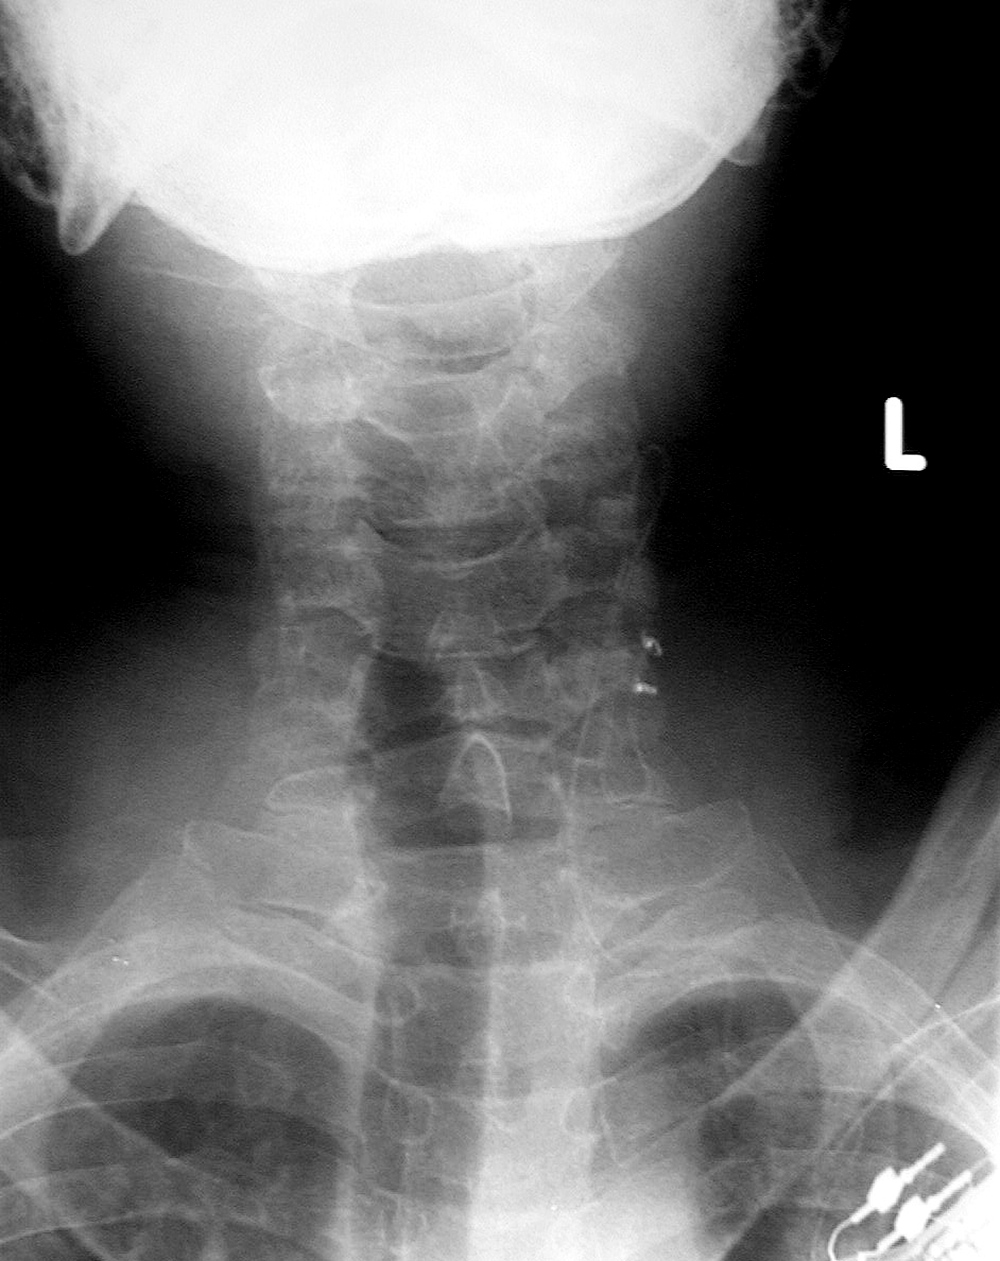

| Cranial tongs (AP view) |

| Child with severe intracranial and cervical spine injuries with bilateral cranial stabilization tongs, an endotracheal tube, an oroogastric tube, and a feeding tube entering via the nose.

From Hunter, 2004 |